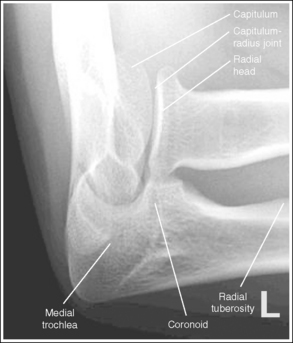

The capitulum-radius joint is either partially or completely closed, and the radial head articulating surface is demonstrated. The olecranon process is situated within the olecranon fossa, and the coronoid process is visible on end.

• The anatomical relationships of the elbow on an AP forearm projection are slightly different from those on an AP elbow projection because of the difference in centering of the central ray. The central ray is placed directly over the elbow joint for an AP elbow projection but is centered distally to the elbow joint, at the midforearm, for an AP forearm projection. With distal centering, diverged rays record the elbow joint image instead of straight central rays, much the same as if the central ray were angled toward the elbow joint. Imaging the elbow with diverged rays projects the radial head into the capitulum-radius joint and causes the anterior margin of the radial head to project beyond the posterior margin, demonstrating its articulating surface.

The distal humerus is in a lateral projection. The distal humerus demonstrates three concentric (having the same center) arcs, formed by the trochlear sulcus, capitulum, and medial aspect of the trochlea. The elbow joint space is open, and the radial head is superimposed over the coronoid process.

• A lateral proximal forearm projection is obtained by placing the elbow in a lateral projection and abducting the humerus until it is parallel with the IR, thereby putting the entire arm on the same horizontal plane. The wrist and hand are then placed in a lateral projection, and the medial (ulnar) aspect of the forearm rests against the IR (see Figure 4-64). Even though the capitulum is placed anterior to the medial trochlea and the humeral epicondyles are not superimposed for this position, an open joint space may still be obtained. Because the central ray is centered to the midforearm, the diverged x-rays used to image the distal humerus align parallel with the slant of the capitulum and medial trochlea (see Figure 4-63). The result of this parallelism is an open elbow joint space.